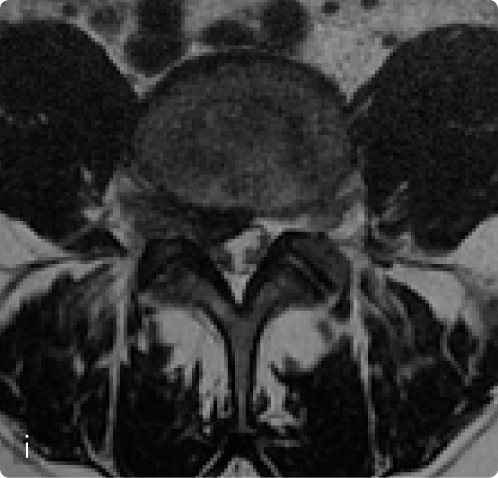

L’indicazione chirurgica è stata occasionalmente posta anche in presenza di sindromi da ernia del disco in pazienti non artrosici (i,l), qualora si fossero presentati all’osservazione in fase compressiva o deficitaria, o in fase irritativa qualora vi fosse una resistenza alla terapia conservativa.